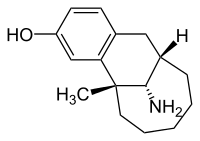

Morphinans

Morphinan series

- 3-Hydroxymorphinan

- 4-Chlorophenylpyridomorphinan

- Cyclorphan

- Levargorphan

- Levorphanol

- Levophenacylmorphan

- Levomethorphan

- Methorphan (racemethorphan)

- Morphanol (racemorphanol)

- Norlevorphanol

- N-Methylmorphinan

- Oxilorphan

- Phenomorphan

- Proxorphan

- Ro4-1539

- Stephodeline Xorphanol

Structures

| Other morphinans | ||||

|---|---|---|---|---|

4-chlorophenylpyridomorphinan 4-chlorophenylpyridomorphinan |

Cyclorphan Cyclorphan |

Dextrallorphan Dextrallorphan |

Levargorphan Levargorphan |

Levophenacylmorphan Levophenacylmorphan |

Levomethorphan Levomethorphan |

Norlevorphanol Norlevorphanol |

N-Methylmorphinan N-Methylmorphinan |

Oxilorphan Oxilorphan |

Phenomorphan Phenomorphan |

Dextromethorphan Dextromethorphan  levomethorphan levomethorphan |

Morphanol Morphanol |

Ro4-1539 Ro4-1539 |

Stephodeline Stephodeline |

Xorphanol Xorphanol |